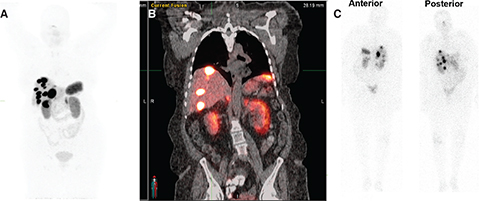

Radiation safety precautions after receiving 177Lu-DOTATATE therapy

Radiation safety precautions for patients after receiving 177Lu-DOTATATE therapy are to restrict the dose received by patients’ family members to less than 5 mSv in 5 years and to members of the public to less than 1 mSv per year. Patients receive oral and written radiation safety precautions for three days after receiving therapy. Blood and urine are the main sources of contamination during and after radionuclide administration. 177Lu-DOTATATE is excreted primarily in urine, therefore, the foremost focus for the first 3 days after therapy is to prevent urinary contamination (46). During this time, a double flush of the toilet is recommended after urination. Patients should wash their hands after using the bathroom. The RADAR website has an online tool that allows the calculation of cumulative doses to family members or members of the public from exposure to patients treated with 177Lu-DOTATATE (47). In addition to the beta particles, 177Lu-DOTATATE also emits two gamma rays (113 KeV and 208KeV) with low relative abundance (6.2% and 10.4% respectively) (48) (Figure 5).

Fig 5

Figure 5. 74-year-old female with advanced and inoperable metastatic ileal NET. A. 68Ga-DOTATATE MIP image and B. Fused coronal image show multiple intensely somatostatin receptor-rich tumors in the liver and portocaval lymph node. C. Post-therapy emission scan acquired 7 days after 117Lu-DOTATATE therapy (anterior and posterior images) Somatostatin receptor rich tumor in liver and a portocaval lymph node.